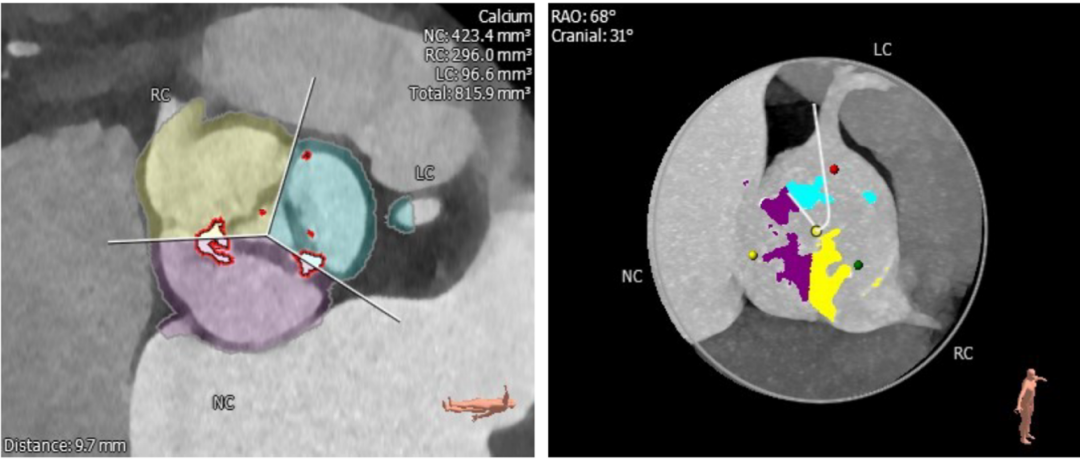

CT评估:

瓣环周长83.5mm,平均直径26.6mm,左室流出道周长85.5mm,平均直径27.2mm,升主动脉直径37.3mm,STJ直径33.3mm,左冠高度12.7mm,右冠高度14.7mm。

瓣环结构:瓣环底部有钙化,延伸至流出道,为功能性二叶瓣;右无及左无交界有明显钙化融合,右无更严重,角度48°,钙化积分815.9mm。